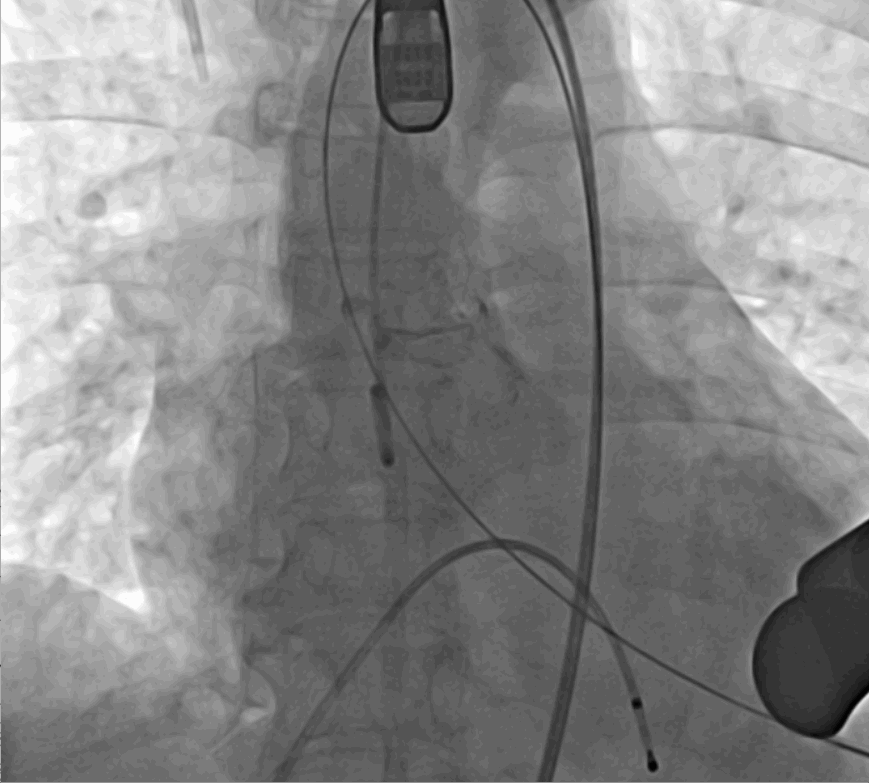

術(shù)前DSA影像圖

術(shù)中釋放定位鍵后DSA影像圖